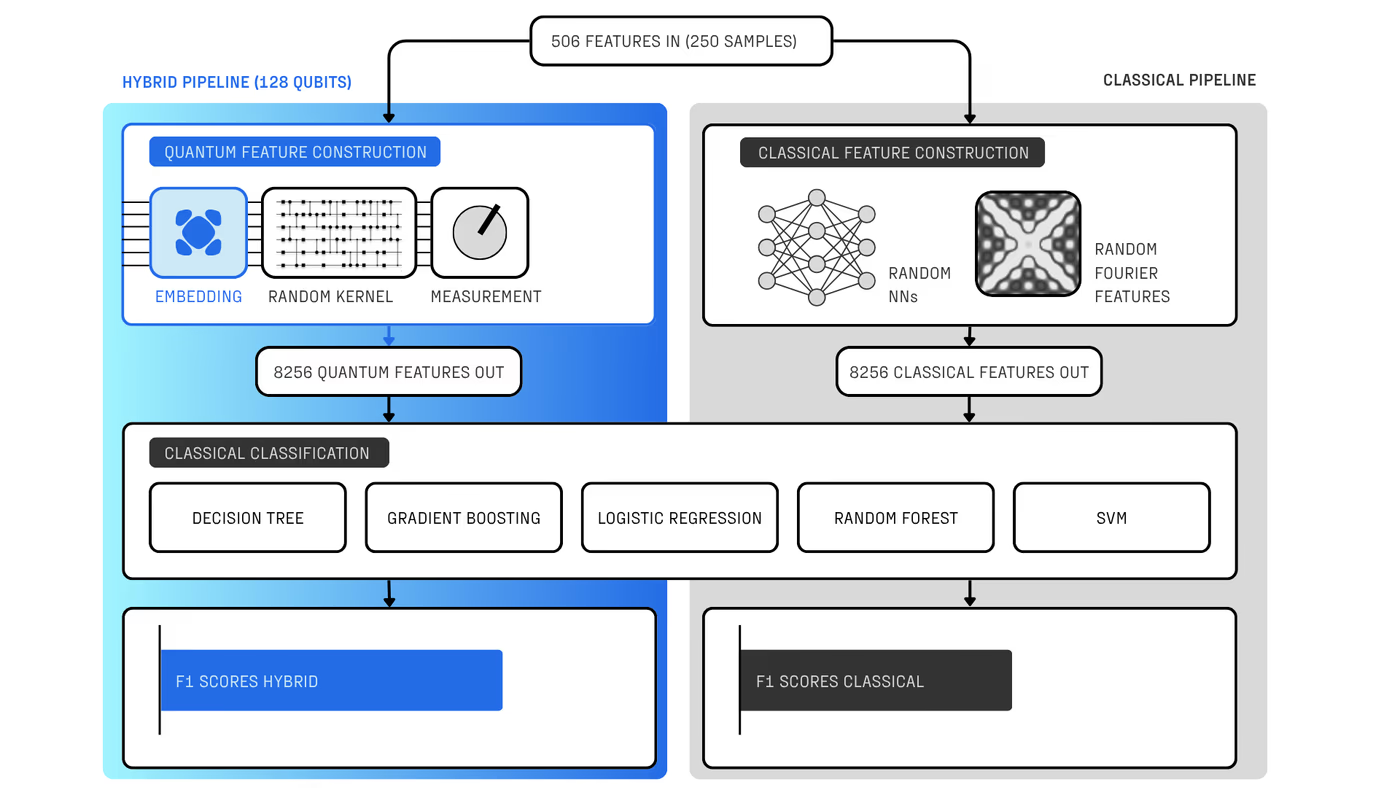

With R&D costs exceeding $2B per drug, pharma increasingly combines machine learning and computational chemistry to accelerate discovery. A powerful approach uses first-principles calculations to generate “quantum fingerprints”—physically grounded features that improve reactivity prediction. However, classical simulation methods scale poorly: they rely on approximations that are either too inaccurate to capture critical many-body effects or too expensive for practical screening.

Quantum computing offers a solution, but until now has been constrained by hardware noise, limiting usable circuit depth to a few hundred two-qubit gates. Haiqu, working with Capgemini, IBM, and GSK, broke this barrier by demonstrating one of the largest electronic-structure Hamiltonian simulations ever run on real quantum hardware for covalent drug warheads. Using advanced circuit compression and middleware execution, the team initially reduced circuit depth by 15.5× and further allowed end-to-end execution by running sub-circuits up to 371 gates.

- Generate predictive quantum features unavailable to classical methods

- Integrate quantum simulations directly into machine-learning-driven discovery pipelines